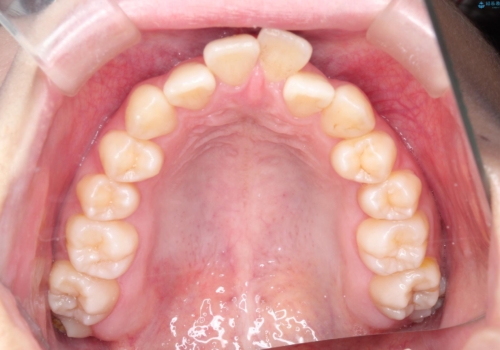

ガタガタも改善しましたが、前歯が内側に引っ込むことにより口元もすっきりして、唇が閉じやすくなりました。